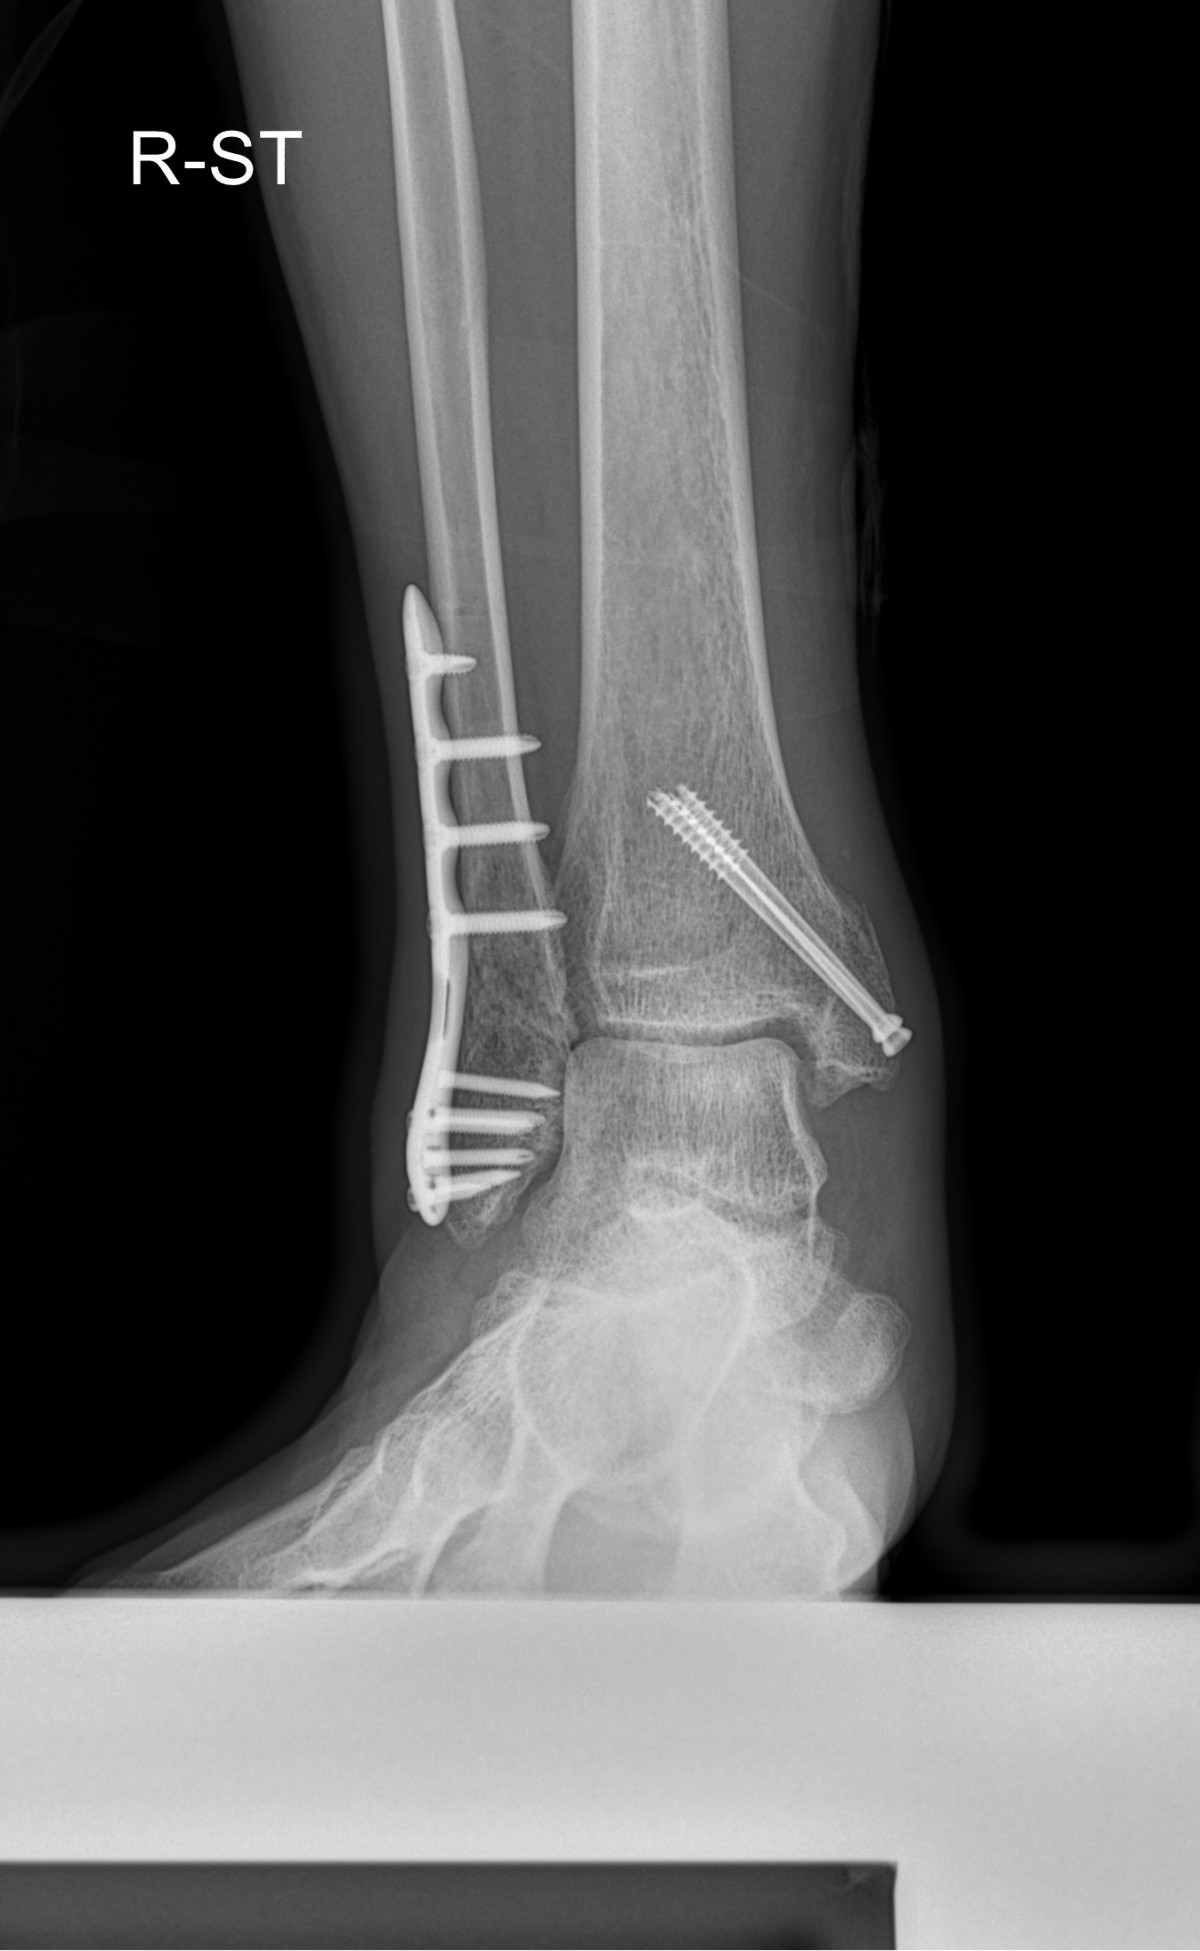

이재상원장님 발목 골절 수술 박근O 환자

dae765e4d9ac96aee867c9d6292d8784_1758002110_0625.jpg